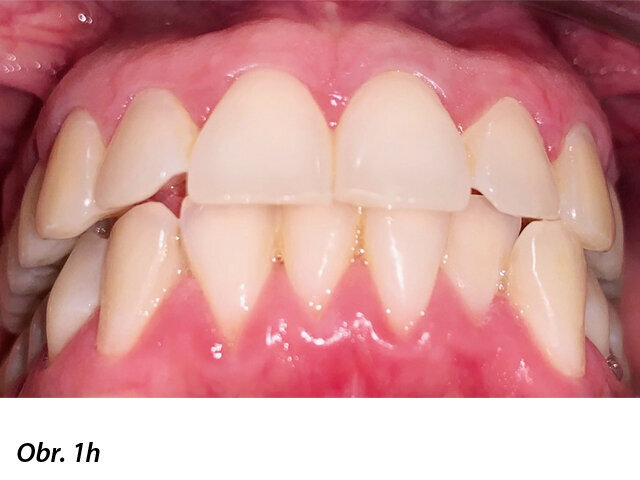

Pacientka 1 – Počáteční fotografie.